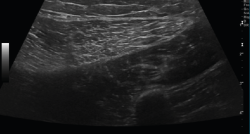

Ecografía

El ultrasonido se puede usar en el diagnóstico de numerosas patologías y puede guiar en procedimientos diagnósticos y terapéuticos(5).

Su indicación fundamental es en el diagnóstico de las lesiones de partes blandas superficiales.

Las estructuras específicas más adecuadas para este estudio incluyen tendones, músculos y ligamentos, además de masas periarticulares de tejidos blandos. Es útil para el diagnóstico de derrame articular, engrosamiento sinovial, bursitis, cuerpos libres intraarticulares, gangliones, quistes, roturas ligamentosas y tendinosas, tendinitis y fracturas ocultas(6).

En el estudio musculoesquelético se utiliza una sonda lineal con alta frecuencia, de entre 9 y 13 mHz.